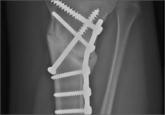

Complete Closing Wedge Osteotomy for Correction of Blount Disease (Tibia Vara): A Technique

Treatment of Blount disease (tibia vara) can be daunting in adolescents because of their obesity.